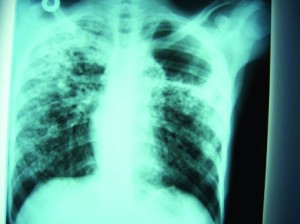

Heart disease is very prevalent in Haiti. The most common condition seen is congestive heart failure. The etiologies are multiple. Peripartum cardiomyopathy is very prevalent in that country. The frequency of this condition is as high as that noted in some West African countries. Valvular heart disease is very common in Haiti. The most common cause of valvular heart disease in Haiti is Rheumatic Heart Disease.

Pericardial disease is also extremely common. The most common etiology of pericardial disease in Haiti is infectious. Tuberculosis is endemic in this population. The complication of pericardial effusion in patients with active tuberculosis is seen fairly frequently. Cardiac imaging with cardiac ultrasound is essential in the diagnostic evaluation of these patients.

Although the diagnosis of heart failure can be made as easily at the bedside, it is impossible to separate heart failure with preserved left ventricular function from heart failure with decreased ventricular function without ultrasound imaging. These conditions are treated quite differently. The severity and the type of valvular heart disease cannot be assessed without the use of cardiac ultrasound. Finally, the diagnosis of pericardial effusion, including its severity, depends on cardiac ultrasound imaging.